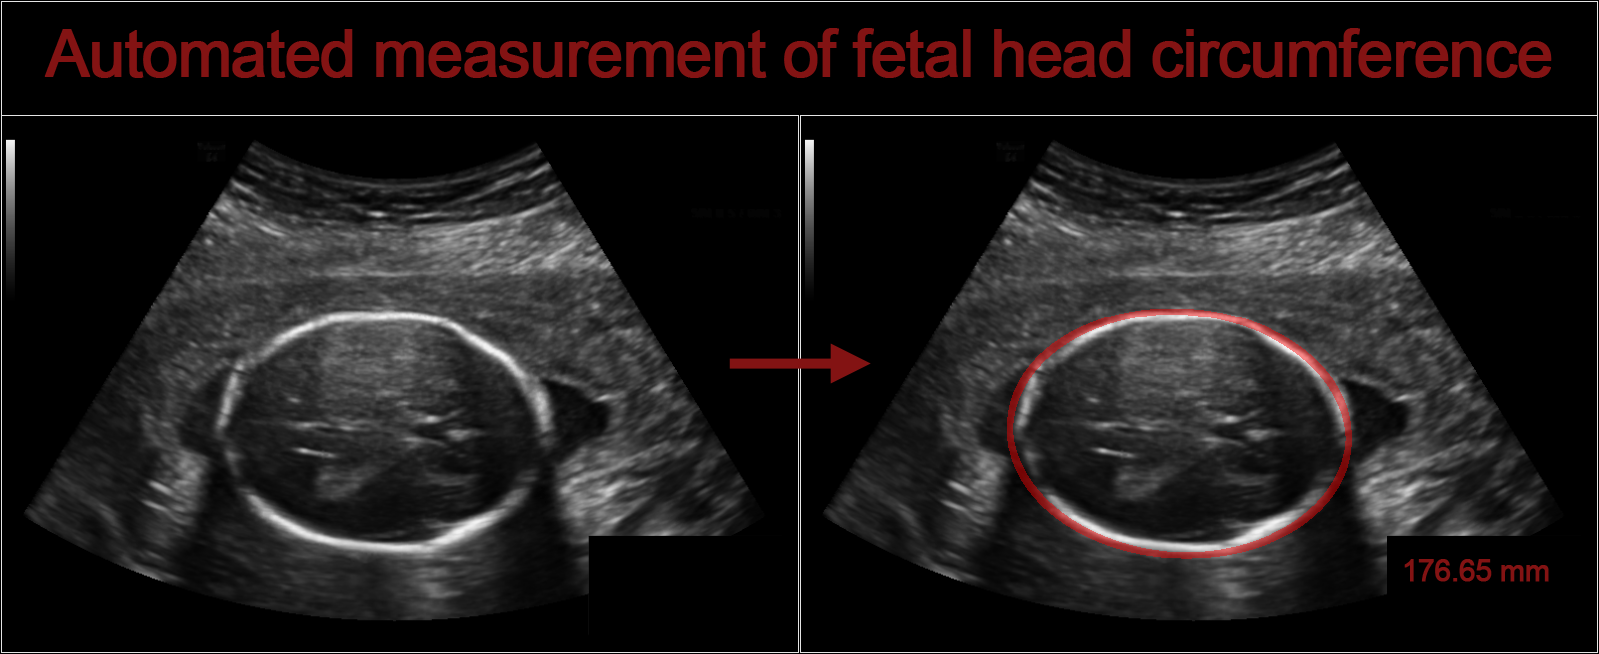

During pregnancy, ultrasound imaging is used to measure fetal biometrics. One of these measurements is the fetal head circumference (HC). The HC can be used to estimate the gestational age and monitor growth of the fetus. The HC is measured in a specific cross section of the fetal head, which is called the standard plane. The dataset for this challenge contains a total of 1334 two-dimensional (2D) ultrasound images of the standard plane that can be used to measure the HC. This challenge makes it possible to compare developed algorithms for automated measurement of fetal head circumference in 2D ultrasound images.

This challenge is aimed to design an algorithm that can automatically measure the fetal head circumference given a 2D ultrasound image. You can use the 999 ultrasound images and the corresponding annotations in the training set to develop an algorithm that can automatically measure the HC. The developed algorithm should be applied to the independent test set of 335 images. You can upload your results on the test set under the Submit tab. The results will be immediately evaluated upon submission and displayed on the leaderboard under the Results tab. This gives you the possibility to compare your algorithm to other algorithms on the same independent test set.